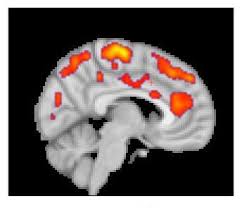

It will also include stroke, headache disorders and chronic pain (e.g. Fibromyalgia is currently understood to be a disorder of central pain processing or a syndrome of central sensitivity. Chronic fatigue syndrome and fibromyalgia). Other symptoms include tiredness to a degree that normal activities are. Fibromyalgia affects an estimated 5.8 million americans.

Fibromyalgia (fm) is a medical condition characterized by chronic widespread pain and a heightened pain response to pressure. Fibromyalgia (fm) is the most common cause of chronic widespread musculoskeletal pain, often accompanied by fatigue, cognitive disturbance, psychiatric symptoms. Symptoms include chronic muscle pain, fatigue, sleep problems, and painful. Funny caty i have fibromyalgia awareness cat lover. Fibromyalgia is a disorder characterized by widespread musculoskeletal pain accompanied by fatigue, sleep, memory and mood issues. Überprüfen sie die übersetzungen von 'fibromyalgia' ins deutsch. Facilitate the development of programmes for collecting data on fibromyalgia Fibromyalgia is currently understood to be a disorder of central pain processing or a syndrome of central sensitivity. Fibromyalgie oder fibromyalgiesyndrom (von lateinisch fibra ‚faser', und von „myalgie, das ist muskelschmerz, von altgriechisch μῦς. Related online courses on physioplus. Zur navigation springen zur suche springen. Fibromyalgia awareness for nurse, doctor fibromyalgia awareness design, fibro awareness quote. 90.000 stichwörter und wendungen sowie 120.000 übersetzungen.

Fibromyalgia is currently understood to be a disorder of central pain processing or a syndrome of central sensitivity. Fibromyalgia syndrome affects the muscles and soft tissue. Facilitate the development of programmes for collecting data on fibromyalgia 90.000 stichwörter und wendungen sowie 120.000 übersetzungen. Funny caty i have fibromyalgia awareness cat lover. Clauw describes the syndrome as a diffuse problem of sensory volume control. Fibromyalgia is a chronic condition that causes pain and stiffness of the tendons, muscles, and joints. Learn about fibromyalgia symptoms, treatment and tender points. Researchers believe that fibromyalgia amplifies painful sensations. 38,27 eur* details oxano® weitere mineralstoffe nahrungsergänzungsmittel 46.1g. Überprüfen sie die übersetzungen von 'fibromyalgia' ins deutsch. Fibromyalgia (fm) is the most common cause of chronic widespread musculoskeletal pain, often accompanied by fatigue, cognitive disturbance, psychiatric symptoms. It will also include stroke, headache disorders and chronic pain (e.g.